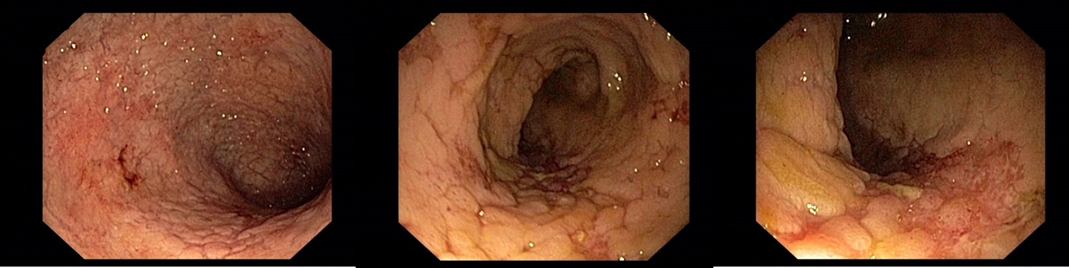

2012/10 Endoskopický obraz mírné segmentální kolitidy charakteru Crohnovy choroby (rozsah postižení je 10-20 % tračníku) - podstatné zlepšení proti předchozímu nálezu, ke slizničnímu zhojení nedošlo

Koloskopie: Endoskopický obraz těžké segmentální kolitidy

2013/11 endoskopický obraz těžké pankolitidy charakteru Crohnovy choroby   - obraz cobble stones relativně je ušetřeno rektum, kde je ložiskově patrná   podslizniční cévní kresba

Koloskopie: Endoskopický kolitidy s ušetřením rekta, maximálním postižením v P tračníku – dle obrazové dokumentace zlepšení ve všech etážích tračníku   (i v P tračníku rozsah ulcerací snížen cca o 50%)

Koloskopie: edém, eroze, ulcerace, zánětlivé polypy v terénu po zánětlivých změn